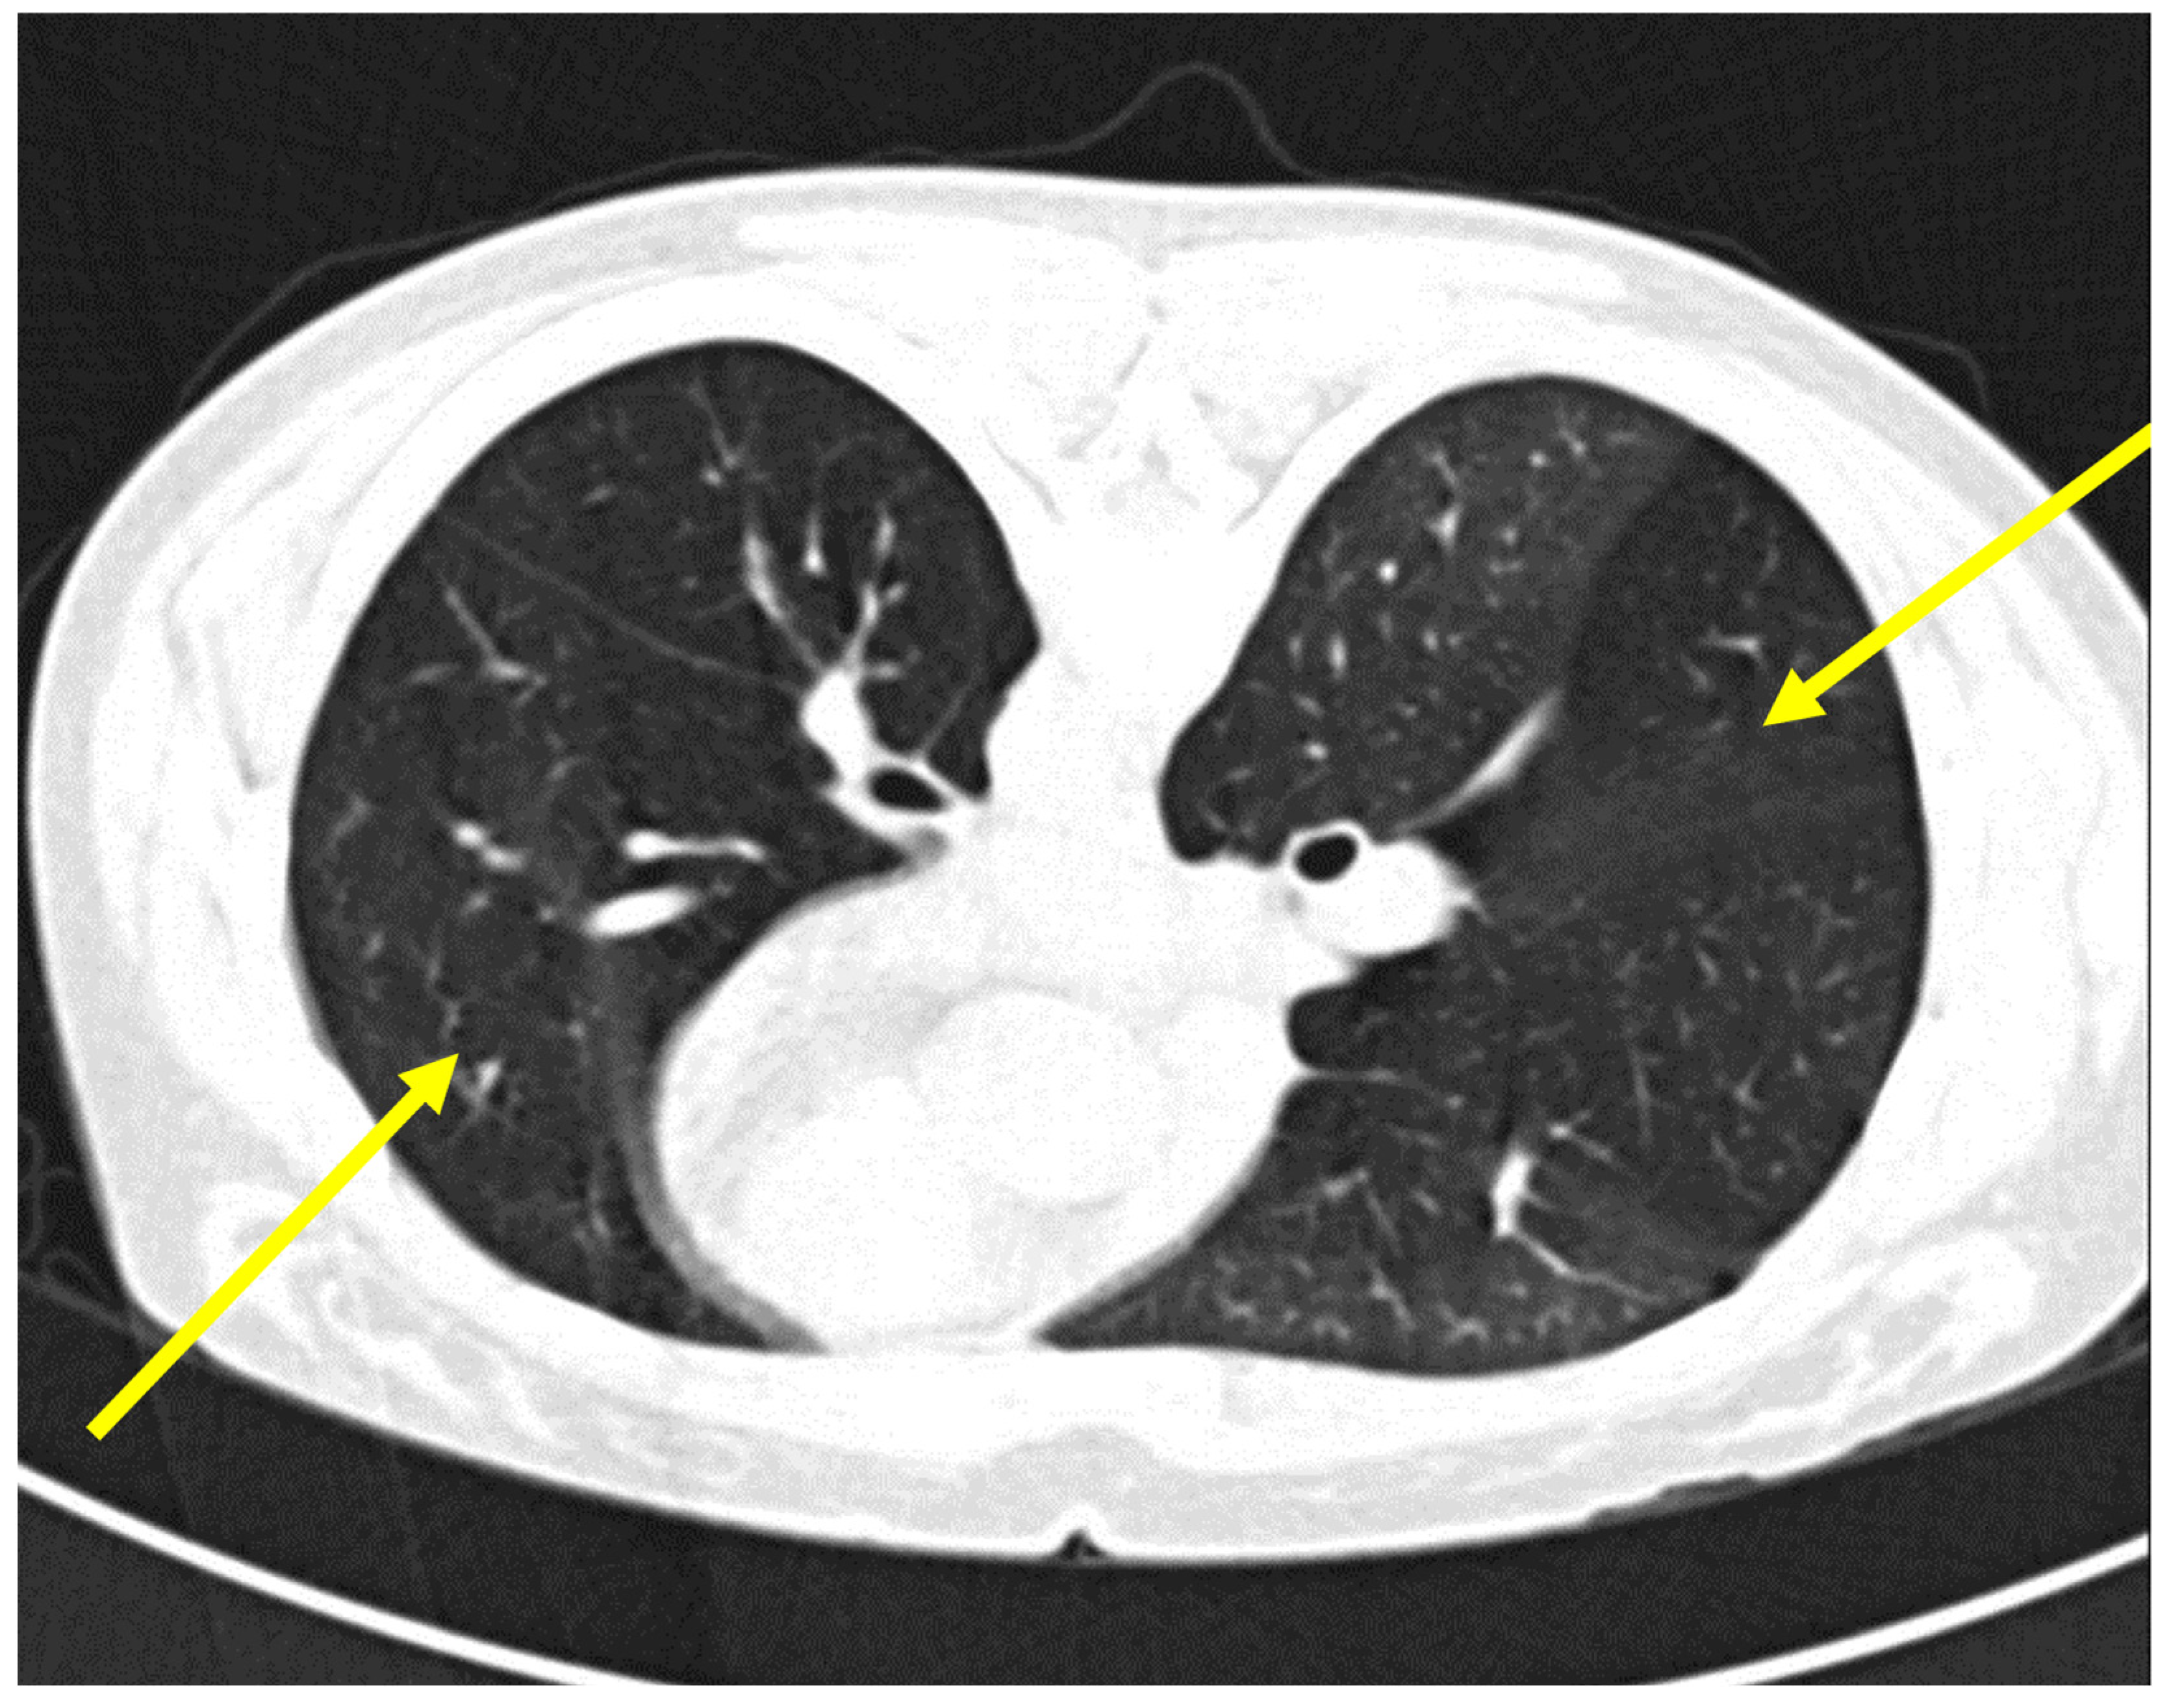

Upon presentation at our department, the patient was in no respiratory distress but did require oxygen supplementation via a nasal cannula due to mild respiratory insufficiency. Lung-function tests revealed her FEV1 to have further diminished to 10% as well as showing evidence of advanced small-airway disease. A high-resolution CT scan (HRCT) of the chest showed a mosaic attenuation pattern at end-expiration (Figure 2). In light of the patient’s respiratory condition, a transbronchial biopsy was considered a high-risk procedure and was therefore omitted.

Figure 2.

High-resolution computed tomography (HRCT) scan of the chest demonstrating features of bronchiolitis obliterans. Mosaic attenuation pattern, characterized by areas of differing lung density. This is most prominently seen in the right lower and left upper lobes (indicated by yellow arrows), where geographic areas of hypoattenuation suggest air trapping due to small airway obstruction.

Bronchiolitis obliterans (BO) manifests as progressive dyspnea and airflow limitation, with diagnosis established by pulmonary function testing mainly by observing severe obstruction and decrease in FEV1, high-resolution CT imaging demonstrating air trapping in end-expiration, and, when feasible, histology. BO is largely refractory to immunosuppression, and while tumor resection may prevent further autoimmune stimulation, respiratory decline often progresses. Differential diagnoses include infectious and autoimmune-related bronchiolitis and interstitial lung diseases, which must be ruled out by clinical and radiological evaluation.